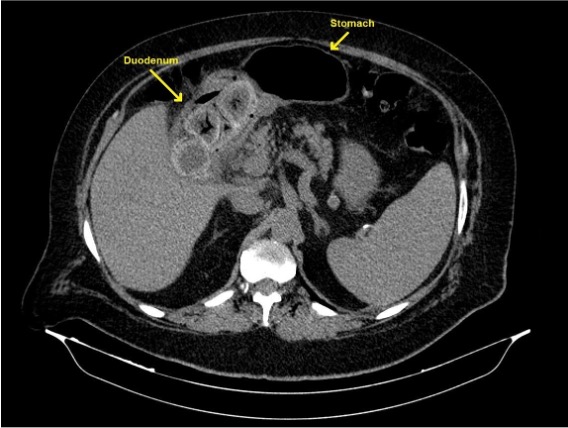

We present a case of a 65-year-old male that presented to the emergency department due to a 3-day history of vomiting and abdominal pain. He also complained of postprandial fullness, anorexia, and weight loss in the past 3 months. He had a history of cholelithiasis and was on the waiting list for cholecystectomy. On examination, he had a distended, tender abdomen in the upper quadrants and right iliac fossa. Laboratory test results showed a mild neutrophilic leukocytosis, anemia, and C-reactive protein of 3.99 mg/dL (normal range <0.5 mg/dL). Abdominal ultrasound performed in the emergency department showed multiple hypodense hepatic nodules, cholelithiasis without signs of cholecystitis and heterogeneous intragastric content. Subsequently, he performed a CT abdominal scan which showed large gallstones impacted in the duodenum, causing gastric outlet obstruction (Bouveret’s syndrome). It also suggested the presence of a cholecystoduodenal fistula (Figure 1). No dilation of small bowel loops or any intraluminal content was identified. He was admitted for additional study. For better characterization of the liver lesions, an abdominal MRI was performed, characterizing the liver nodules as hemangiomas. Also, several dilated fluid-filled small bowel loops could now be observed, and a large gallstone was found in the ileum, suggesting migration of one of the previously identified in the duodenum on the initial CT scan. In the stomach, another gallstone could be identified. (Figure 2). Esophagogastroduodenoscopy showed one large black stone of 6-7cm in the distal antrum. The patient underwent an exploratory laparotomy with intra-abdominal examination, and two stones were identified, one at the gastric level and the other at the distal ileum, close to the ileocecal valve. Gastrolithotomy and enterolithotomy were performed with stone removal. The patient recovery was unremarkable.

Figure 1: Unenhanced axial CT slice showing large gallstones impacted in the duodenum, causing gastric outlet obstruction (Bouveret syndrome). The gallbladder was contracted, suggesting that a cholecystoduodenal fistula had been formed, from which the stones passed to the duodenum.